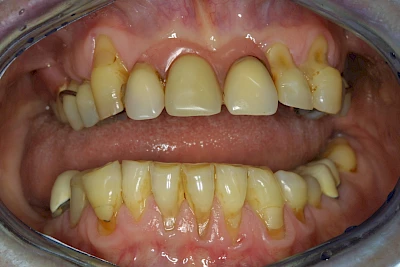

Keilförmiger Defekt

Eine Sonderform sind sogenannte keilförmige Defekte im Bereich der Zahnhälse. Hier geht man davon aus, dass Knirschen und Pressen in Kombination mit falschen Putzgewohnheiten (zu hoher Putzdruck, Verwendung von Zahnpasta mit hohen Abrasionswerten) eine Rolle spielen.